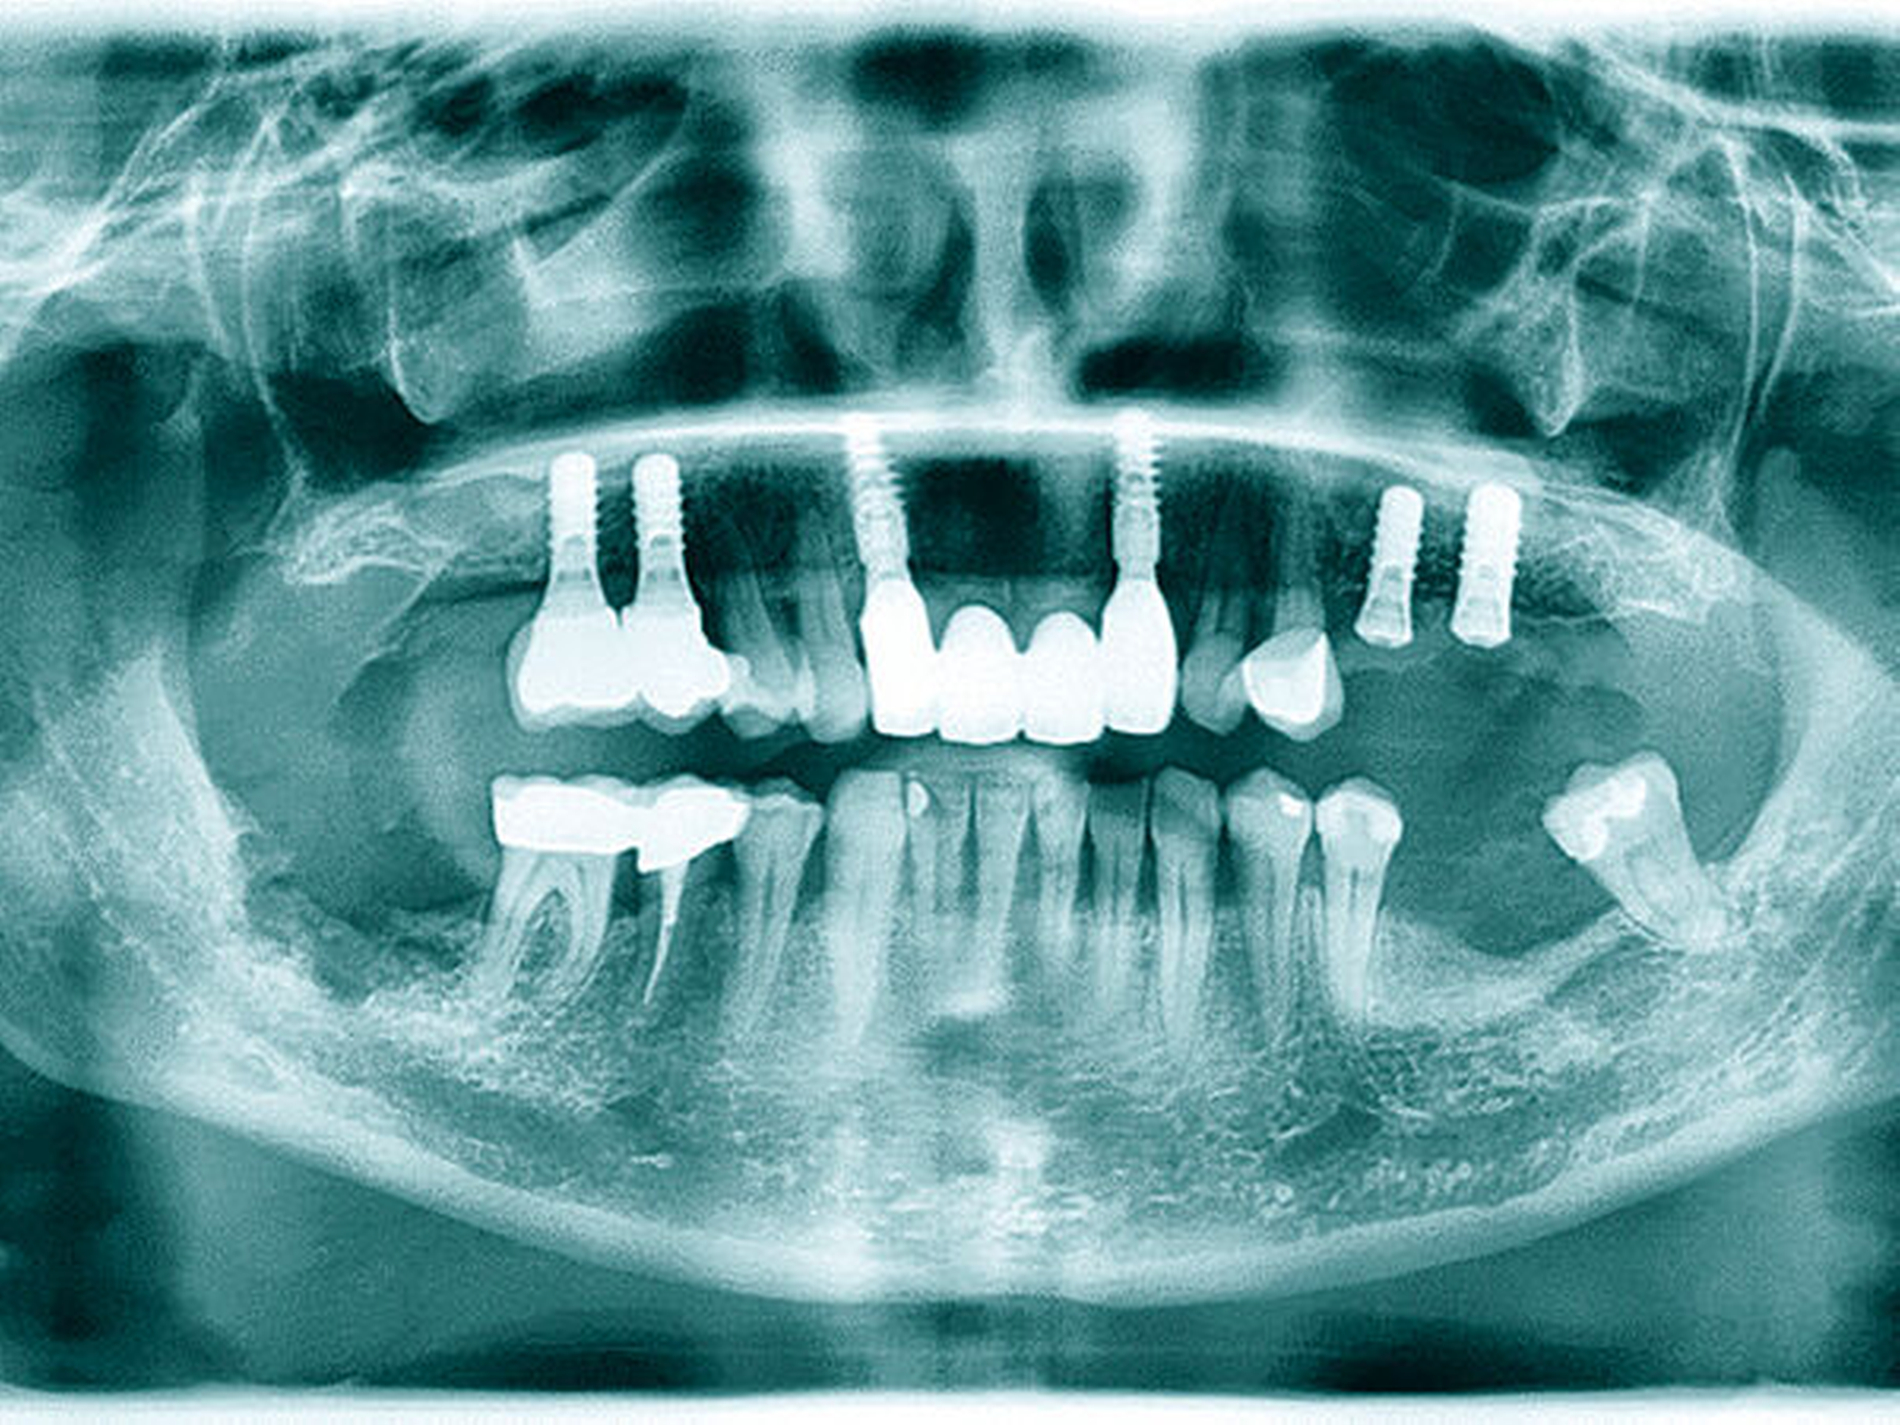

In den Abbildungen 6 bis 9 sind mehrere Fälle mit langem Beobachtungszeitraum dargestellt. Beachtenswert ist vor allem der zu beobachtende vollständige Umbau des Knochens inklusive der Ausbildung einer neuen Kompakta. Die augmentierten Bereiche sind nach wenigen Jahren nicht mehr als solche zu erkennen. Die Arbeit mit autologem Knochen ist insbesondere für die Patientengruppe interessant, die bevorzugt nach biologisch sicher verträglichen Behandlungen sucht. Dieser Trend nimmt unseren Beobachtungen nach stetig zu. n